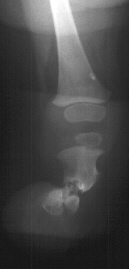

PHYSICAL EXAM: Examination of the right lower extremity demonstrates shortening of the right thigh with a 10 degree flexion contracture present in the knee. The knee is noted to be in valgus. There is moderate anteromedial bowing present in the leg with a dimple present over the anterior aspect of the tibia at the apex of the bow. The foot is held in a position of severe equinovalgus with absence of the lateral two rays noted. There is syndactyly present among the remaining digits. Circulation is normal and skin condition is good. Overall, the right lower extremity is noted to be 5 cm. shortened when compared to the contralateral normal extremity. Attempts at ambulation were limited by the severe deformity present in the right lower extremity.

RADIOGRAPHS: Absent right fibula and lateral two rays of right foot with moderate anteromedial bowing of tibia. The right femur was also noted to be shortened.